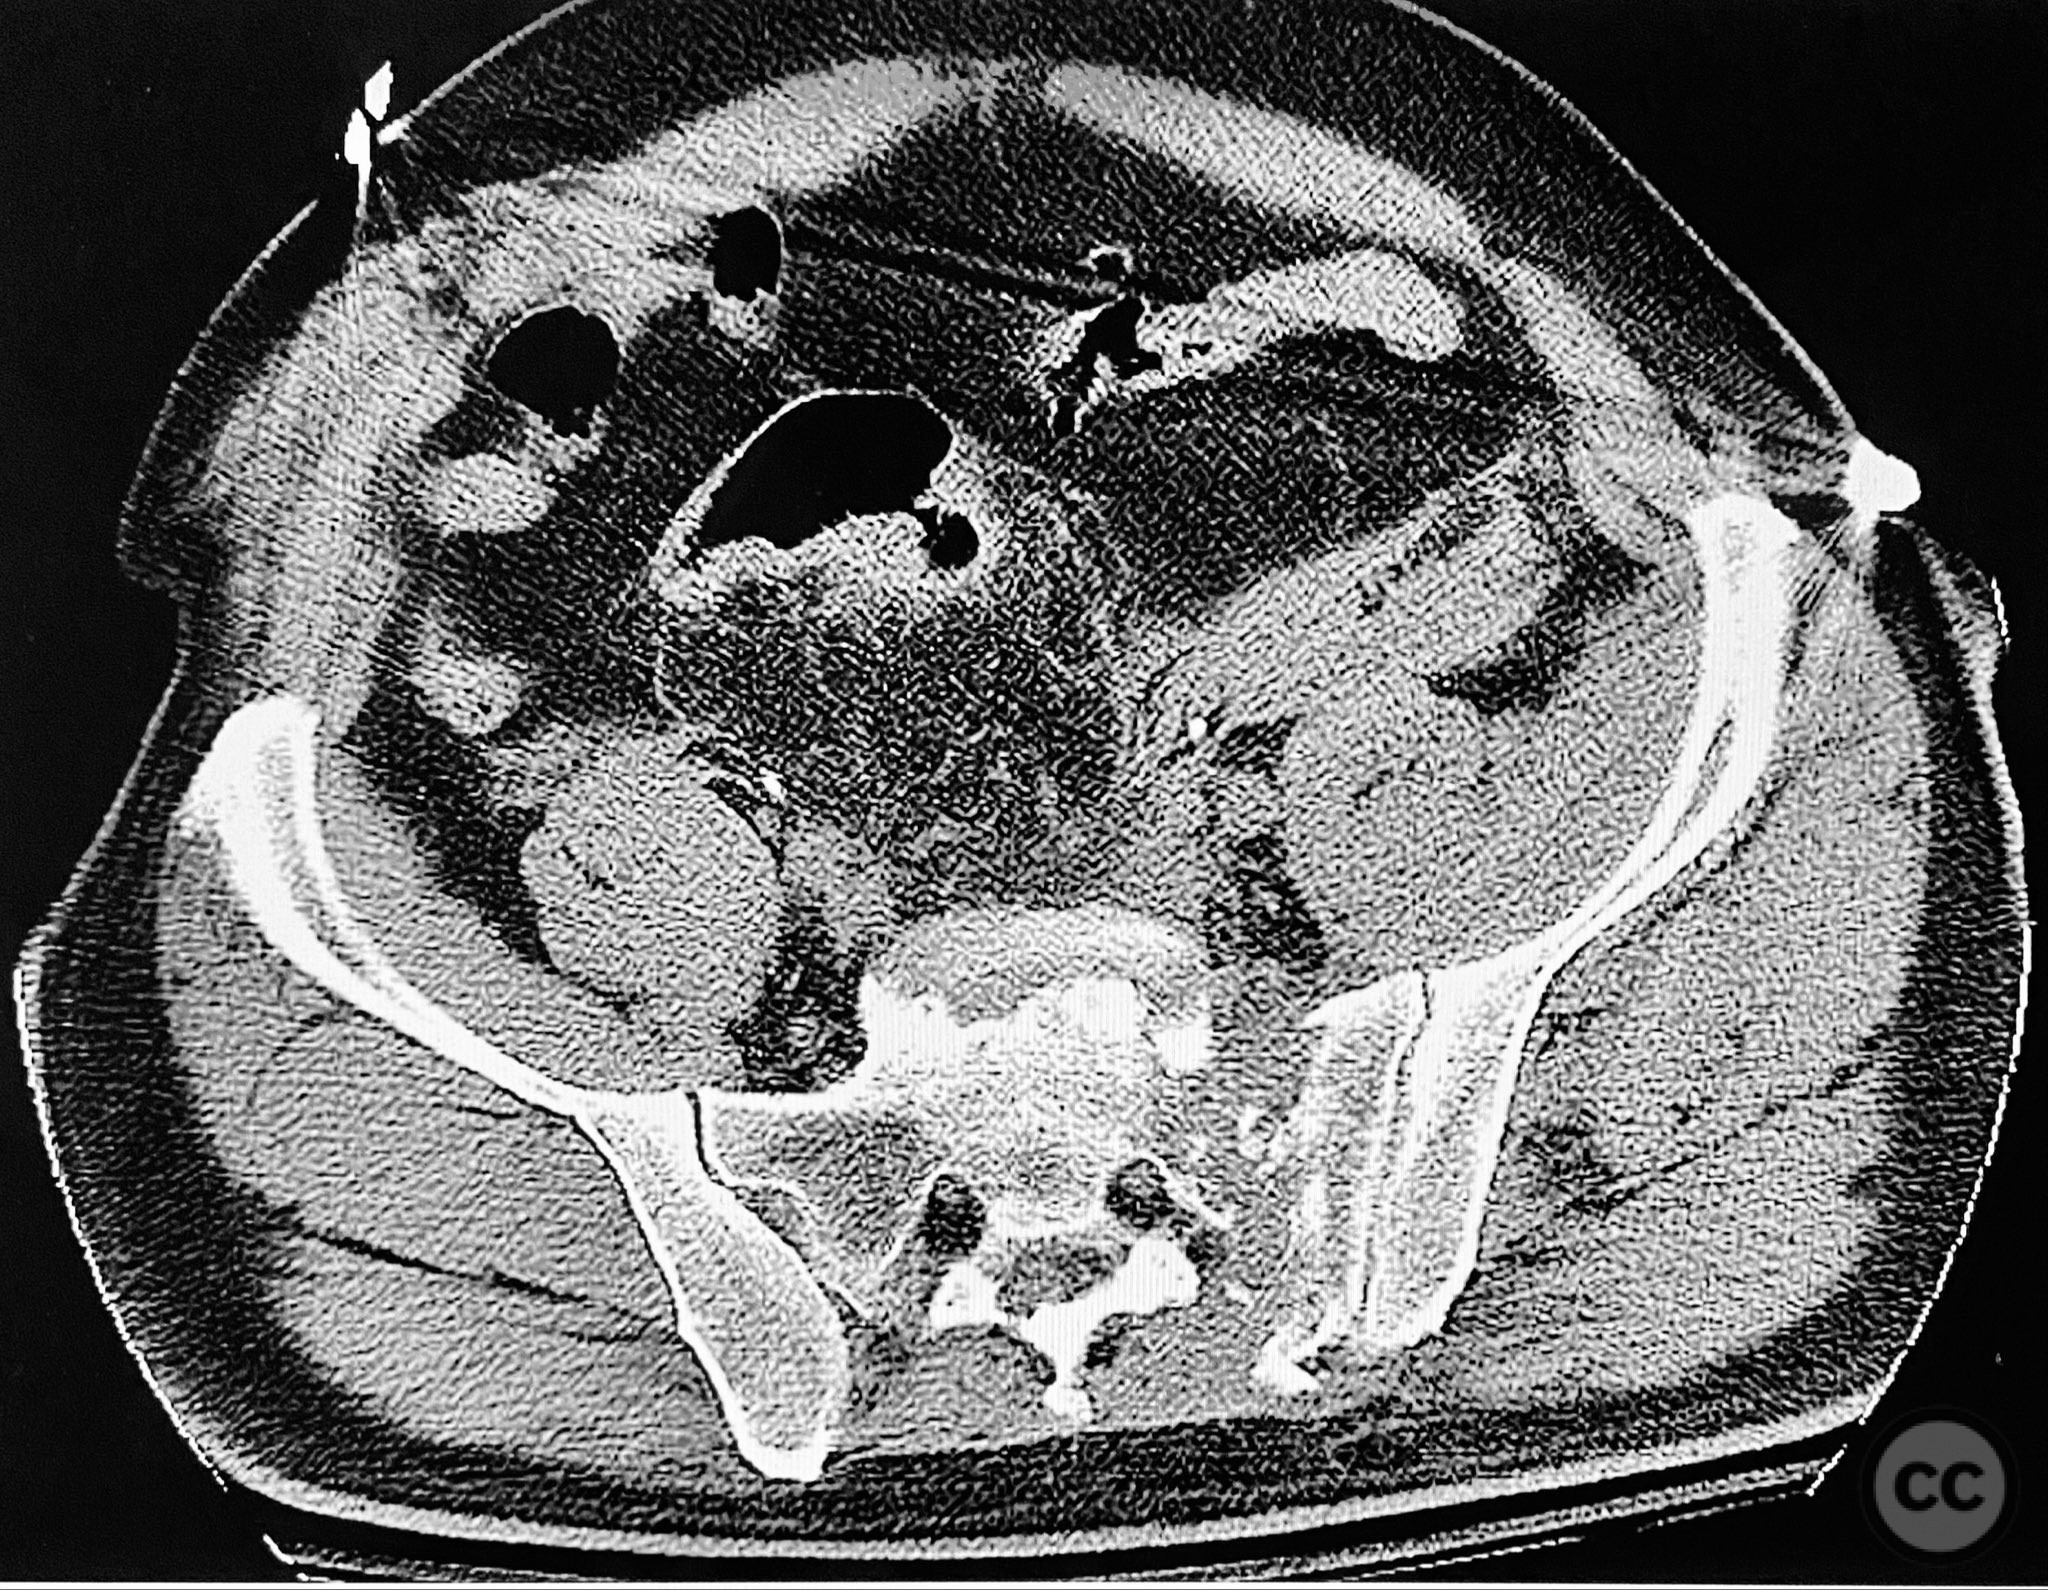

Clinical and radiological findings:  A 54-year-old male presented following a motor vehicle accident with pelvic pain. He was haemodynamically stable and neurologically intact on admission. Initial anteroposterior pelvic radiograph demonstrated disruption of the symphysis pubis, fractures of the left superior/inferior pubic rami, and a left sacral fracture. Circumferential pelvic sheeting improved patient comfort and reduced hemipelvic displacement. Skeletal traction was considered but not yet applied. Computed tomography revealed comminution and displacement of the left sacral fracture, as well as detailed characterization of the anterior ring injuries. AO/OTA classification: 61-C1.3 (displaced, combined anterior and posterior ring injury with complete instability). Young-Burgess classification: APC III.

The posterior reduction was facilitated by direct visualization of the dorsal sacral cortex, allowing precise assessment and clamping of the comminuted fragments prior to screw fixation. The iliosacral screws were placed without cannulated instrumentation longer than 130mm, reflecting historical implant limitations at the time of surgery. Postoperative CT confirmed satisfactory reduction and fixation of the posterior ring, though suboptimal positioning of iliosacral screws was noted (contained within the osseous fixation pathway but not optimized for maximal safety or precision). The anterior ring was subsequently addressed in a staged fashion, with anatomical reduction and stable fixation achieved via open technique. This case highlights technical challenges in achieving optimal screw trajectory and length, particularly with historical implant constraints, as well as the importance of staged management in complex pelvic ring disruptions.